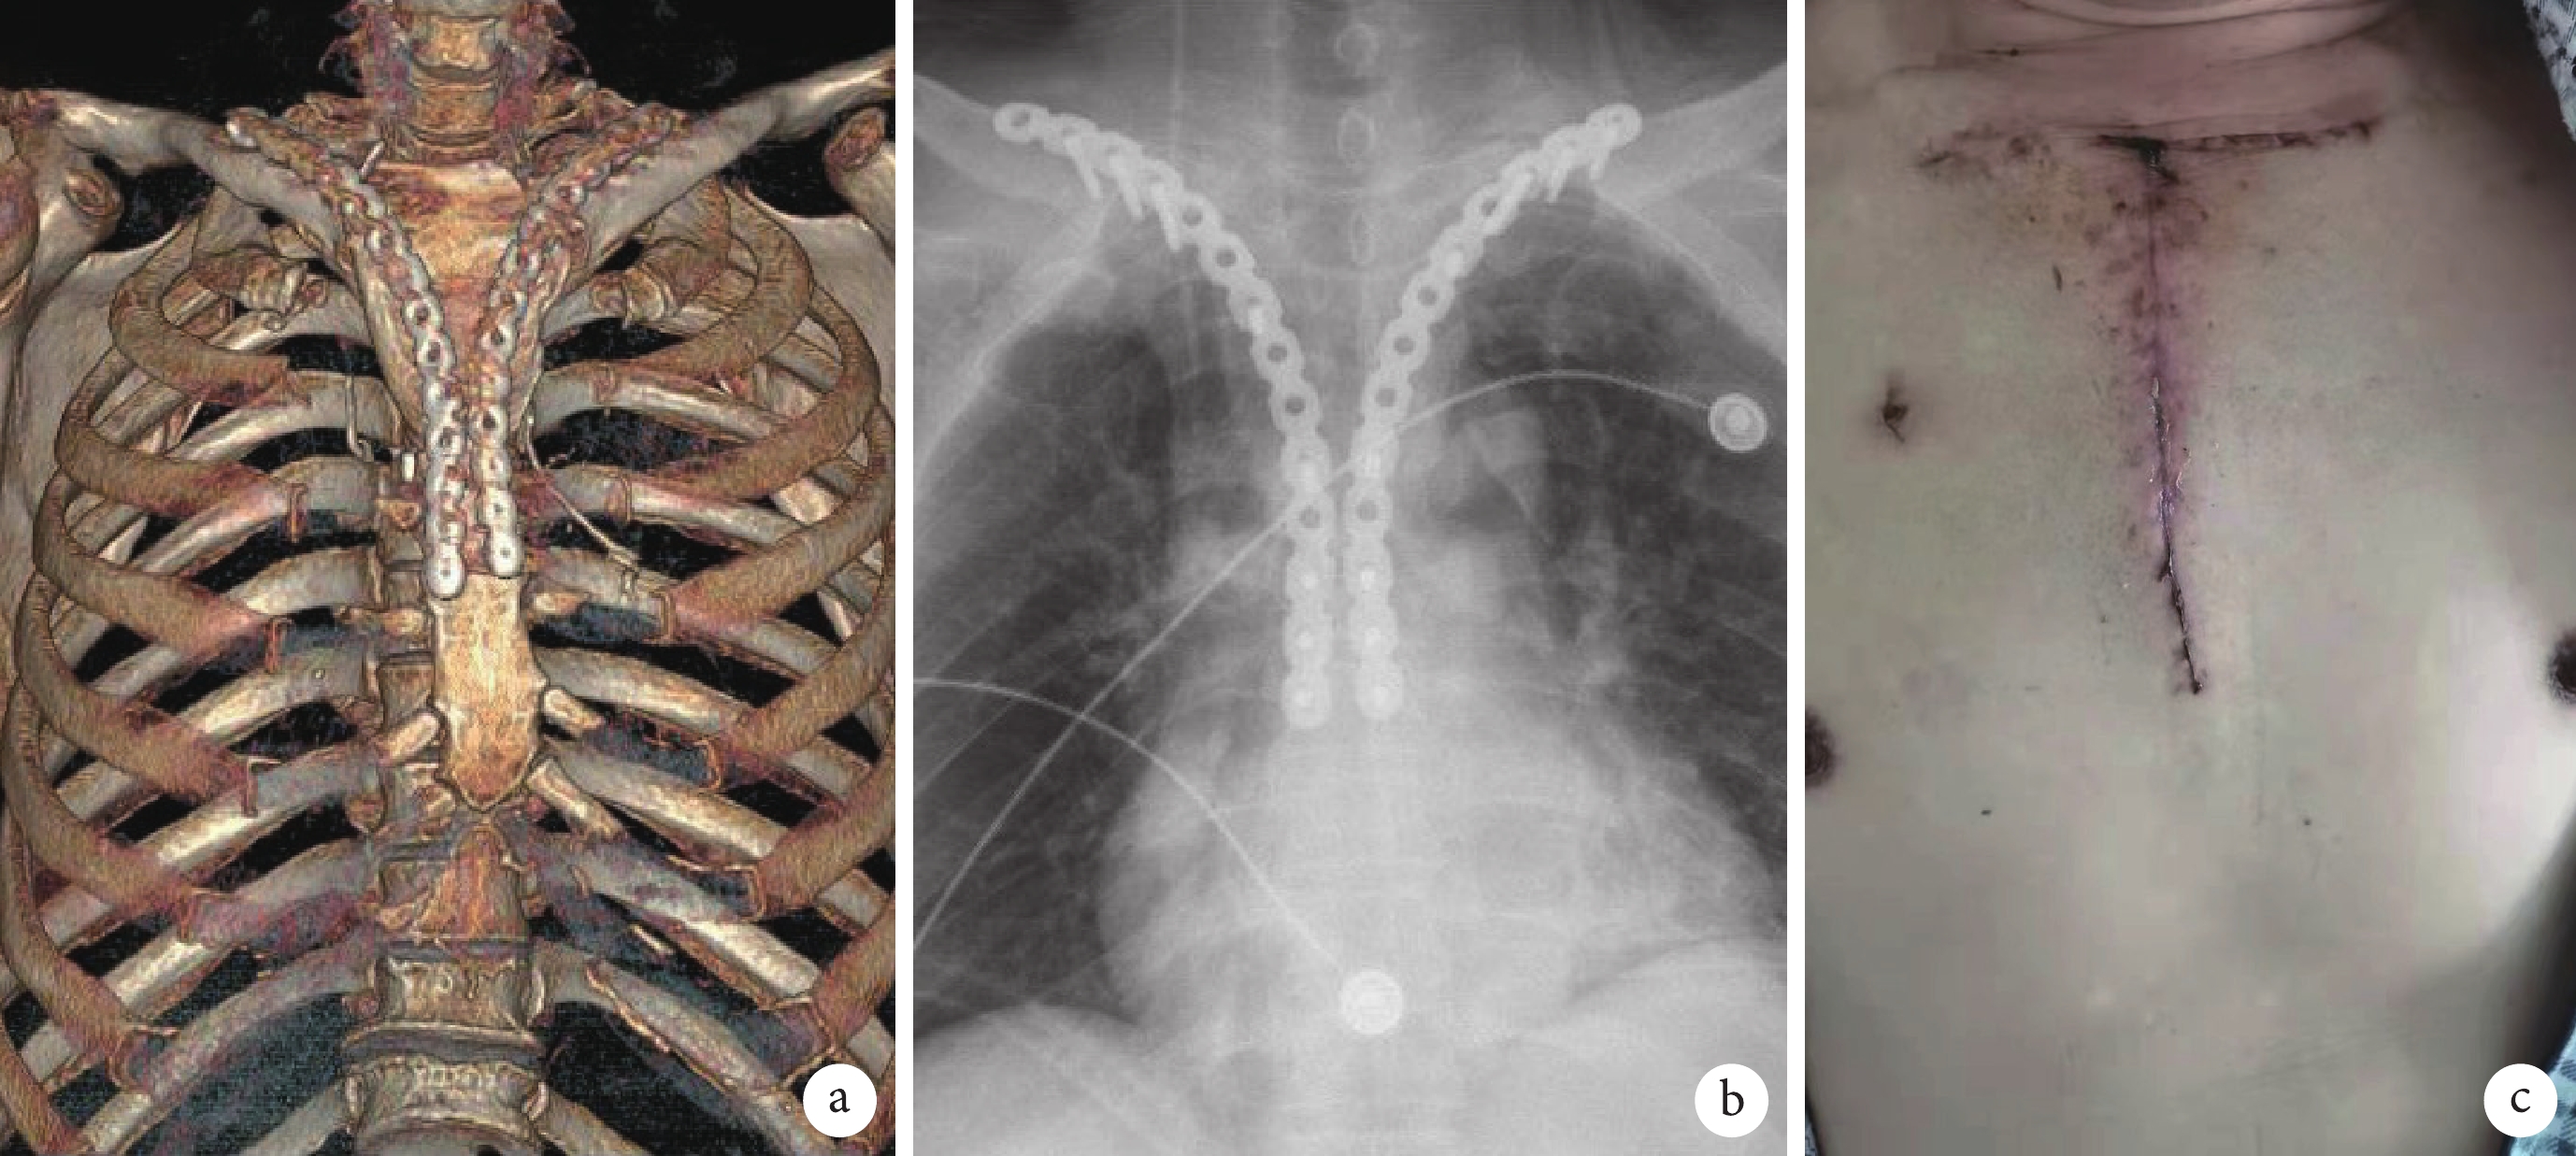

圖3

術后復查

a:胸部三維重建;b:胸部正位片;c:出院前胸廓外形美觀